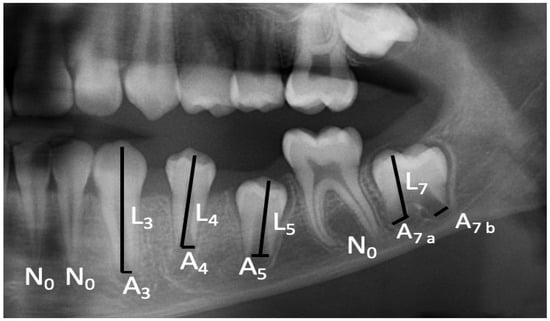

2.6. Dental Age Determination